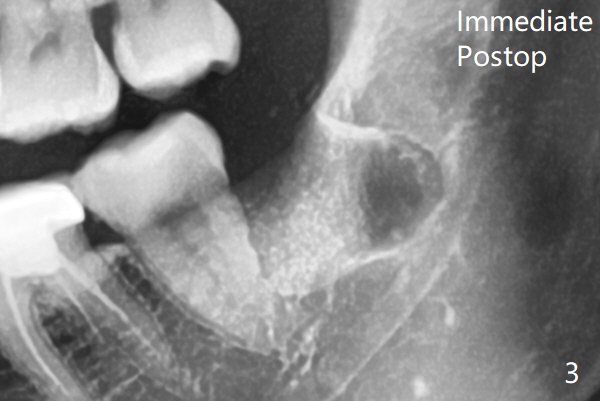

A 31-year-old woman returns with chief complaint of "occasional, mild pain in the lower left 3rd molar" 1 year post extraction of #1 and 16 (Fig.1,2). The lower 2nd molars appears to have a single fused root (Fig.2',2'' S); the radiopaque image mesial to the tooth #32 must be the dense bone (Fig.2' *). In contrast the cortex coronal to the tooth #17 is lacking (Fig.2'' v), as compared to that in Fig.2'. It seems that the bone loss at #17 is associated with mild pericoronitis. The tooth #17 should be extracted with placement of Bond Apatite to repair #18 distal defect. In fact sticky bone and collagen plug are placed instead (Fig.3), covered by 2 pieces of PRF.